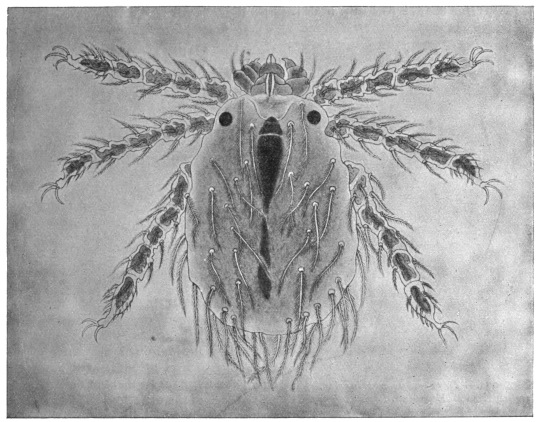

367Sarcoptes scabiei. (After Fürstenberg)518